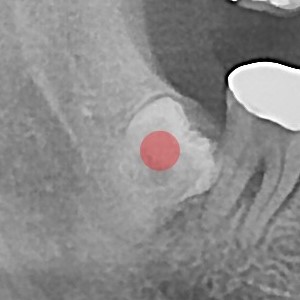

智齿拔除 完全埋伏智齿

b047bd763797d0ee5fe0c71c12970e9f_1766119706_3664.jpg